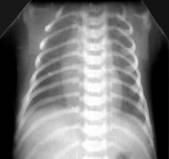

Умеренное снижение пневматизации легких, различимы воздушные бронхограммы, границы сердца чёткие (Рис.4).

Рисунок 4

Рентгенограмма грудной клетки в прямой проекции в горизонтальном положении. (

Диагностика и лечение РДС недоношенных // метод. Рекомендация, 2007)